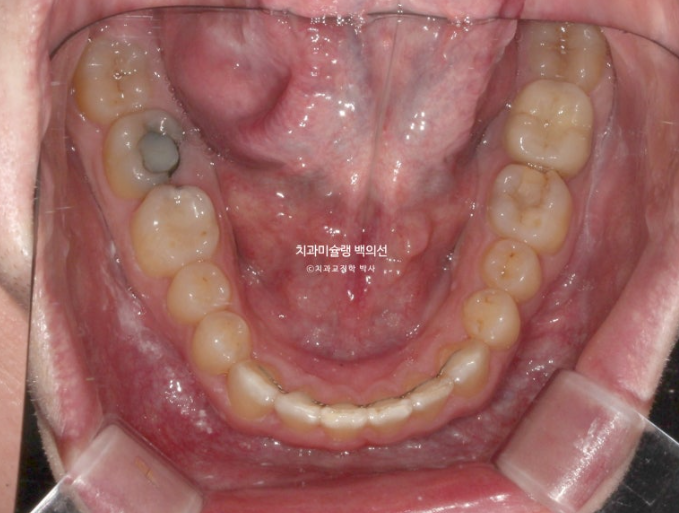

아래는 유지장치까지 붙여서 마무리 한 뒤 임플란트를 심습니다.

25.04

임플란트는 먼저 뿌리를 심고 몇달간 안정화 기간을 거쳐서 치아머리를 만듭니다.

약 6개월간 안정기간을 충분히 가진 후 25년 4월 임플란트 머리를 올립니다.